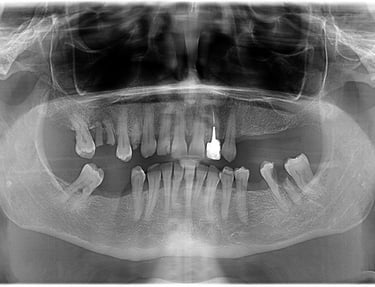

Se deceleaza imagistic o formatiune tumorala radiotransparenta, de mari dimensiuni, localizata la nivelul intregului grup frontal mandibular.

Dupa examenul clinic si imagistic se pune diagnosticul prezumtiv de formatiune tumorala chistica (chist radicular de mari dimensiuni). Se intervine chirurgical realizandu-se extractiile dintilor cauzali, irecuperabili, rezectii apicale a dintilor implicati chistic, care au fost tratati endodontic in prealabil. Piesa operatorie a fost trimisa catre examenul histopatologic, diagnosticul fiind chist radicular fara atipii.